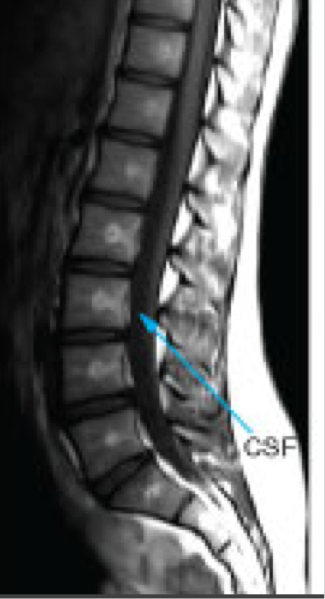

MRI: T1 weighted images

Highlights fat as bright

Muscles as intermediate

Water (blood, CSF) as dark

MRI: T2 weighted images

Highlights water as bright

Fat as slightly less bright

Muscle as intermediate

Brain- white matter is darker than gray matter

Spine MRI

—evaluating soft tissues of the spine, disc herniations and spinal cord injuries, fractures are usually evaluated by CT